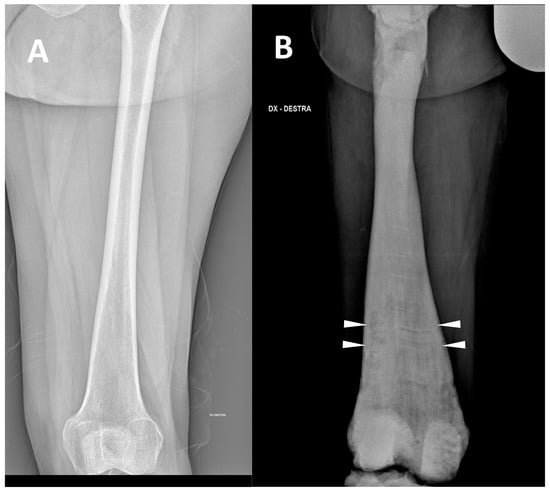

(2) Defects, enlargement/expansion, and other alterations at long bone metaphysis, which appear widened sometimes with a funnel-like shape (the so-called Erlenmeyer flask deformity) (Figure 2).

This sign consists of a lack of modelling of the dimetaphysis with abnormal cortical thinning and a lack of the concave dimetaphyseal curve [15]. This deformity results in a flask-like appearance of long bones. Indeed, this sign was firstly described in the femur, but it could be similarly found in other long bones such as the tibia and humerus. The metaphyseal enlargement/alteration leading to the ‘Erlenmeyer flask deformity’ appearance can be found in ARO, ADO type 2, and IAO osteopetrosis.

The Erlenmeyer flask deformity can also be found in several other conditions, including multiple exostoses disease, metaphyseal dysplasia, Gaucher’s, Niemann-Pick, and achondroplasia [21,22].

Figure 2. (A) conventional radiography of the thigh of a young healthy female (shown as comparison). (B) conventional radiography of the right thigh in a 35-year-old male affected by osteopetrosis (ARO type). Metaphyseal enlargement with the so-called ‘Erlenmeyer flask deformity’ of the distal femur, as well as a diffuse increase in bone radiolucency (increased bone density) are detectable. Alternating lucent and sclerotic metaphyseal banding can also be noted.